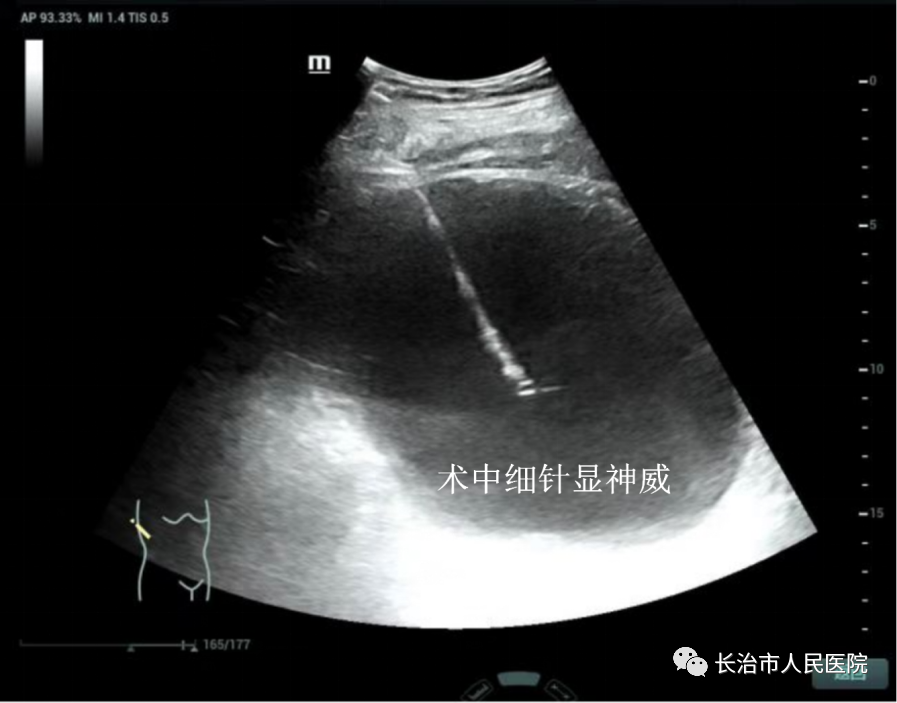

近年来,超声医学技术发展迅猛,尤其是介入超声的发展,迎来了超声从诊断到治疗的里程碑。介入超声以其针过无痕、精准微创等优势获得了临床及患者的认可。10cm大小的肝囊肿,16cm大小的肾囊肿,3cm大小的甲状腺良性结节,0.8cm大小的甲状腺恶性结节,无论其大小良恶,在崔教授精湛的操作技术下,在一根细针的舞动下,在“超声造影”等超声利器的助攻下,短短几分钟或十几分钟,病灶就被“解决”,患者体表只留下一个几乎看不到的针眼。一个巨大肾囊肿患者,术后当场在我院日间手术室门口蹦跳了几下,眉开眼笑,说感觉身体瞬间轻盈了许多。